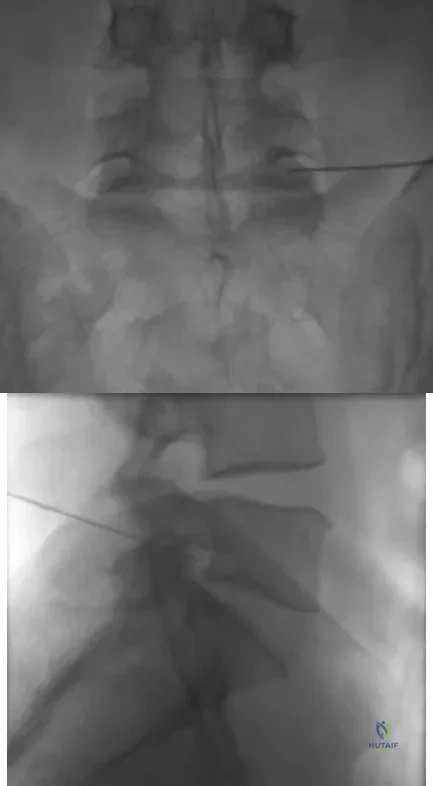

Which of the following factors has the greatest effect on the pull-out strength of a lumbar pedicle screw?

Which of the following patient factors is associated with recurrent radicular pain following lumbar diskectomy for sciatica?

Which of the following mechanisms of inhibition has been linked to cigarette smoking and lumbar spinal fusion?

A patient underwent an anterior cervical diskectomy and interbody fusion for a C5-6 herniated nucleus pulposus and left C6 radiculopathy 8 months ago. He now reports new onset of severe neck pain and left C6 radicular pain, with wrist extension weakness. The radiograph and CT scan shown in Figures 26a and 26b reveal pseudarthrosis at C5-6. The next step in management should consist of

A patient who has had neck pain radiating down the arm for the past 4 weeks reports that the pain was excruciating during the first week. Management consisting of anti-inflammatory drugs and physical therapy has decreased the neck and arm symptoms from 10/10 to 3/10. He remains neurologically intact. MRI and CT scans are shown in Figures 5a and 5b. The best course of action should be